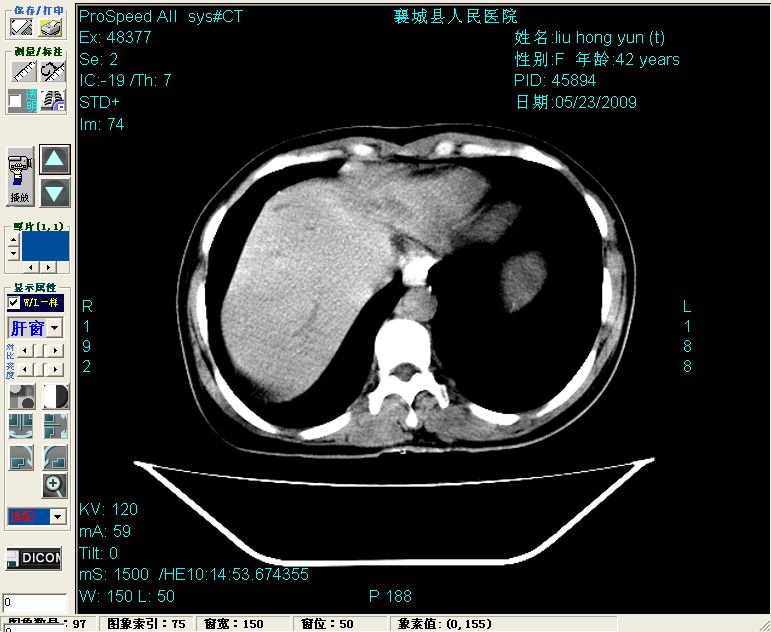

增强:

增强动脉期前述低密度区轻度早其强化,门脉期强化程度显著增高,延期扫描强化程度下降,但仍为相对高密度影

2左肝及右肝前叶表现考虑胆囊摘除术后所致的肝动门脉瘘形成,慢性纤维组织炎性增生.不完全除外左肝胆管细胞癌

1)肝内胆管结石,胆总管末端结石伴肝内胆管扩张。2)肝左叶及肝右叶前段增强前后之异常表现,考虑炎性改变,不排除胆管细胞癌。

1)肝内胆管结石,胆总管末端结石伴肝内胆管扩张。2)肝左叶及肝右叶前段增强前后之异常表现,考虑炎性改变,不排除胆管细胞癌。3)脾大。